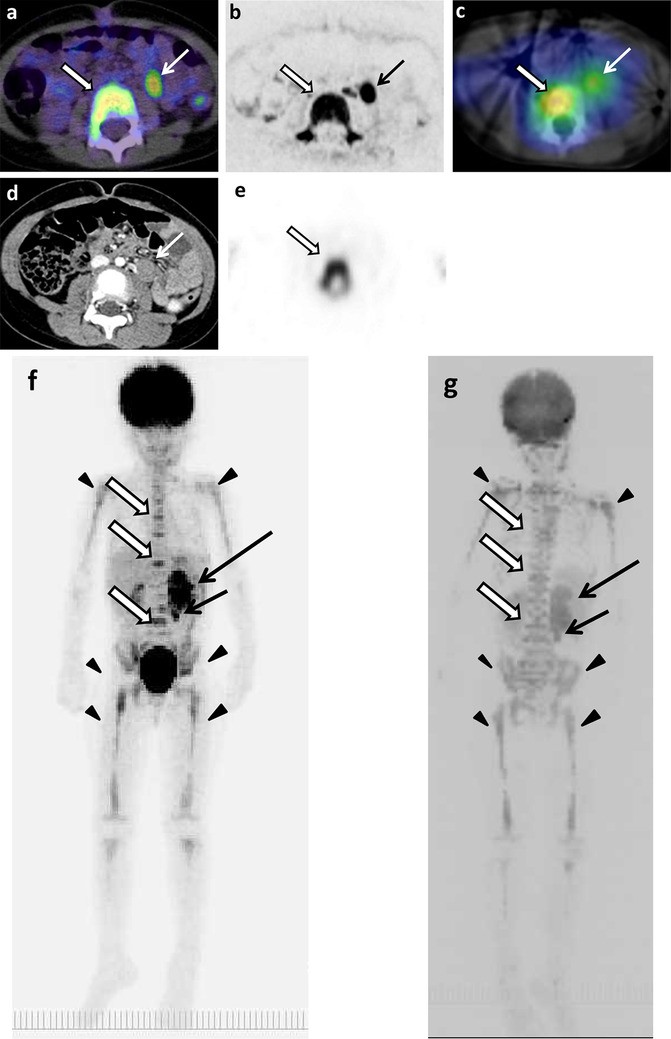

Fig. 3

figure 3

The original lesions in left adrenal gland, metastases in paraaortic lymph nodes and thoracic and lumbar spines, and false-positive images of skeletons of 4 years and 9 months old girl (patient 11). a 18F-FDG PET/CT. b DWIBS. c 123I-MIBG scintigraphy/SPECT-CT. d CT. e Bone scintigraphy/SPECT. The MIP of 18F-FDG PET (f) and DWIBS (g). Long arrows show the original lesion (f, g). Short arrows show lymph node metastases (ag). Empty arrows show bone metastases (ac, eg). Arrowheads show false-positive images of various bone segments (f, g)

The example false-positive images in various bone segments by DWIBS are shown along with the negative results by 18F-FDG PET/CT, 123I-MIBG scintigraphy/SPECT-CT, and bone scintigraphy/SPECT in Figs. 1, 2, 4, 5 and 6. Diffuse intensive false-positive signals by DWIBS are seen in pelvic bones (iliac and sacral bones) (Fig. 4a). Faint diffuse false-positive signals are seen in various bones (Figs. 5, 6).